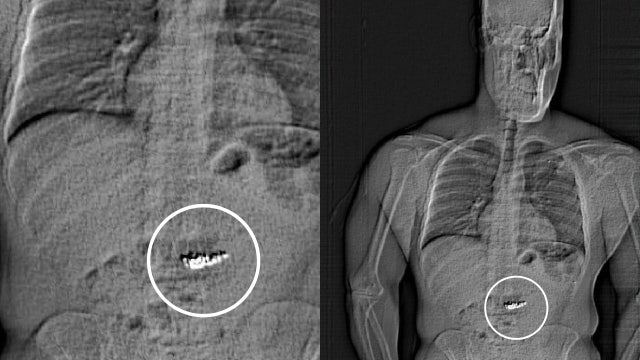

Texas man swallowed $700K in Tiffany earrings during alleged jewelry heist in Orlando, deputies say

A Texas man who claimed to represent an Orlando Magic player interested in purchasing nearly $1 million in jewelry from Tiffany & Co.

Man accused of swallowing luxury earrings

Larry Lawton, a crime prevention specialist, joins FOX 35 to talk about Jaythan Gilder, who was recently arrested for allegedly stealing $769,500 worth of jewelry from Tiffany & Co. at the Mall at Millenia. Authorities say Gilder, who has a history of similar crimes, attempted to swallow the stolen earrings during his arrest and now faces charges of robbery with a mask and first-degree grand theft.